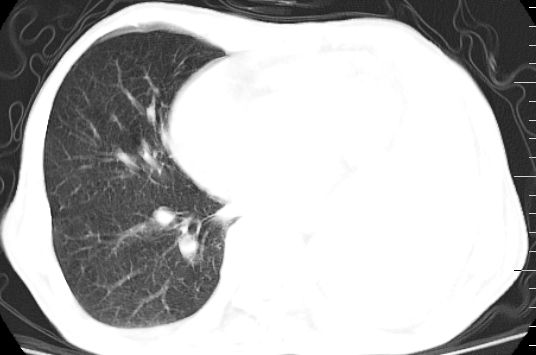

标题: CT10141:男、84岁,咳嗽、咯血1年。 [打印本页]

标题: CT10141:男、84岁,咳嗽、咯血1年。

左下中央型肺癌伴阻塞性不张,肺炎,左侧包裹性胸腔积液\\心包积液

左肺中心性肺癌并左肺下叶肺不张,纵隔淋巴转移、同侧胸腔及心包积液(转移)。

左肺中心性肺癌并肺不张,同侧 胸膜及心包转移,左肺癌性淋巴管炎